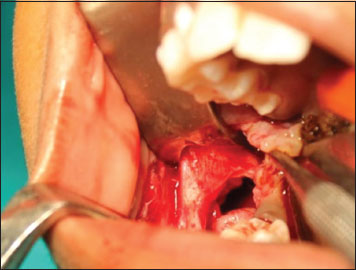

An incisional biopsy was done and it showed epithelial lining with ameloblast-like cells and adjacent connective tissue stroma. There was no luminal proliferation of epithelium, suggestive of intraluminal ameloblastoma [Figure 6]. Following the diagnosis, the parents were informed about the condition and proposed treatment. Surgical enucleation along with chemical cauterization with Carnoy's solution [Figure 7] was done under general anesthesia along with extraction of 47 [Figure 8] considering age of the patient. The patient is under follow-up, with no functional or esthetic complaints. Six months posttreatment, OPG shows signs of new bone formation [Figure 9].

| Figure.7:Surgical site of enucleation

| Figure.8:Surgical specimen with extracted 47